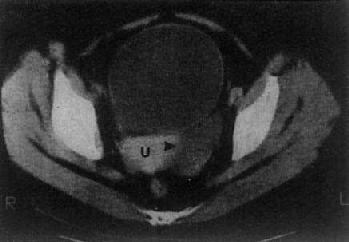

(三)卵巢囊肿或肿瘤 单纯的卵巢囊肿,大多是潴留囊肿,常较小,CT易于显示。表现为囊性低密度影,CT值接近水,边界光滑整齐,大小常为数厘米(图4-5-8)。囊性畸瘤表现为密度不均的低密度肿块,内含多种组织如脂肪、钙化、牙或骨组织皮样囊肿,其壁常有钙化。卵巢囊腺瘤常较大。浆液性囊腺瘤可为单房性或多房性,壁较薄,少数可为双侧性。粘液性囊腺瘤壁较厚,常为多房性。它们的CT值约为15Hu,增强扫描其壁和囊均不增强。卵巢恶性肿瘤表现为盆腔或下腹部肿块,呈软组织密度,CT值40~50Hu,肿瘤大多同时具有实性和囊性部分,边缘不规则,这些有别于良性囊腺瘤和单纯性囊肿,增强扫描实体部分有增强。卵巢癌可产生腹水,其CT值偏高,可达60Hu,30%的病例可见腹膜或大网膜转移,表现为前腹壁后方扁平形软组织肿块,密度不均,境界不清。有时可见腹膜、腹腔内及肠壁间结节肿块。CT检查了解卵巢癌的范围和转移情况比判断原发癌更为重要。

图4-5-8 卵巢囊肿

子宫(U)左侧有一长圆形低密度区(→),边界清楚,其CT值与膀胱CT值相似